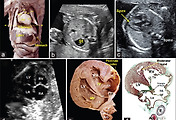

(a) Lateral view of the RA and its appendage, a roughly triangular-shaped offshoot whose apex generally points upward, overlapping the aortic root. (b) The RA and ventricle have been opened like a book to show the different components of the RA, such as the terminal crest and the origin of the pectinate muscles, the vestibule next to the tricuspid valve, the triangle of Koch and the orifice of the coronary sinus. (c) Sagittal section of a 28-week fetal heart showing the coronary sinus which extends through the left atrioventricular groove and is separated from the walls of the LA. (d-f) Frontal sections of a 23-week heart, where image e is a histologic stain using trichromic Masson stain corresponding to image d. Note the different morphology of the right and left atrial appendages and distinguish between the smooth-walled LA and the pectinated RA. Note in image f, the superior interatrial fold between the right pulmonary veins to the LA, and the caval veins to the RA. Ao: Aorta, IVS: Interventricular septum, CS: Coronary sinus, CSO: Coronary sinus orifice, E: Esophagus, EV: Eustachian valve, IVS: Interventricular septum, LA: Left atrium, LAA: Left atrial appendage, LAAO: Left atrial appendage orifice, LV: Left ventricle, LSPV: Left superior pulmonary vein, MV: Mitral valve, OF: Oval fossa, PA: Pulmonary artery, PM: Pectinate muscles, PT: Pulmonary trunk, RA: Right atrium, RAA: Right atrial appendage, RIPV: Right inferior pulmonary vein, RV: Right ventricle, SCV: Superior caval vein, SIF: Superior interatrial fold, TC: Terminal crest, TV: Tricuspid valve